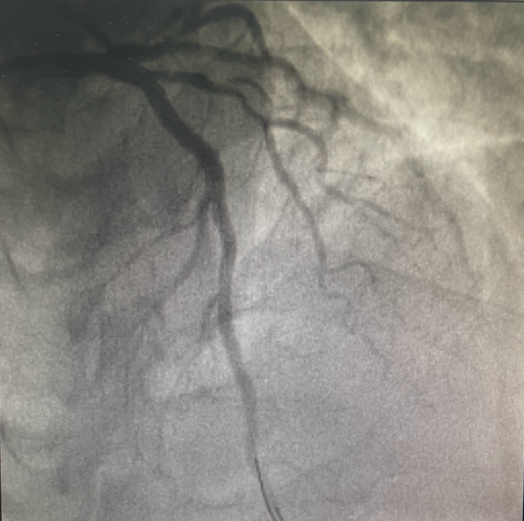

血管开通前

23:32分

血管造影显示:患者“三支血管病变”,前降支近段几乎闭塞,回旋支近段可见80%狭窄病变,右冠状动脉中段慢性闭塞。

血管开通后